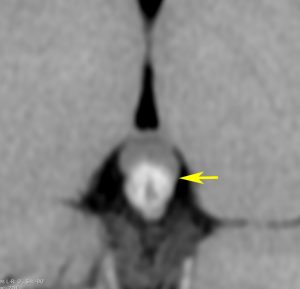

側脳室先端(前角,後角,側頭角,閂),下垂体と大脳基底核に放射線が入らないとその部位から再発します。

再発ジャーミノーマの画像です。延髄背側の閂 ovexという部位に再発しています。

このパターンはとても多いです。なぜかというと,全脳室照射の時に,第4脳室下端のovexの上衣 ependyum を照射野に入れない放射線治療医の先生がいるからです。放射線科の先生にもちょっとした知識が必要なのです。

これは再治療で腫瘍が消えても不可逆的な重症の延髄障害を残してしまいます。